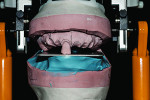

The deflasked dentures should remain on the master cast or be placed back onto it to assess whether they accidently moved during the deflasking process. The case was remounted and post-process equilibrated (Figure 11). This step is crucial in the fabrication of the prosthesis to evaluate any changes to occlusion that may take place during curing, especially when using the press-packing technique. After the case was equilibrated, it was removed from the master casts and polished (Figure 12). This was to ensure no stone or putty would remain anywhere on the case. The dentures still were not fully finished because a Gradia gum facing needed to be added in order to create a more natural appearance.